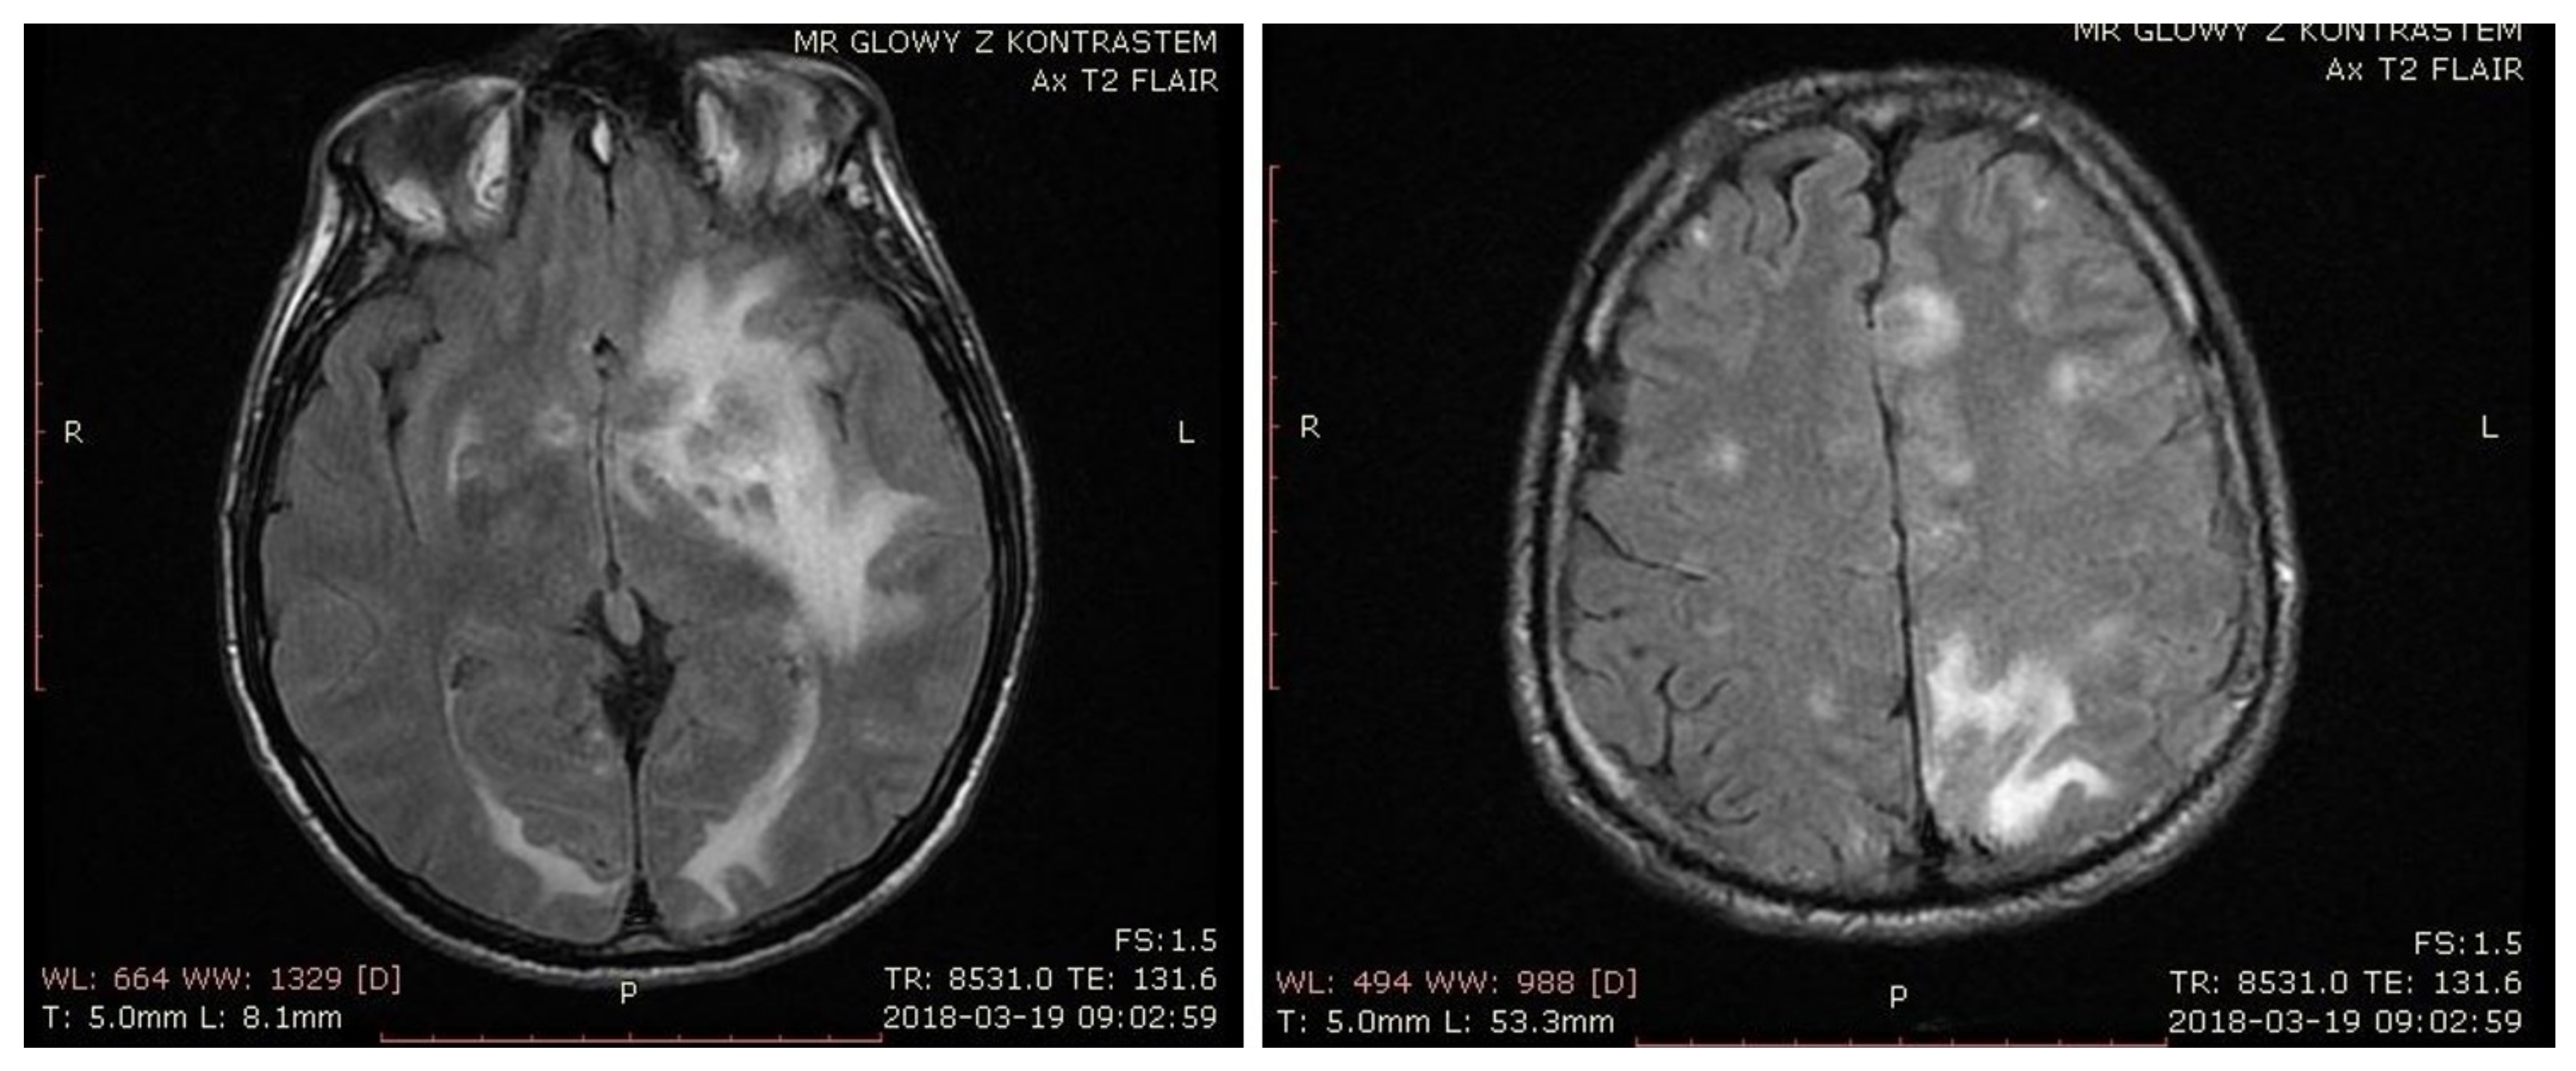

In March 2018, the patient presented with altered levels of consciousness, aphasia, and hemiparesis. On admission to the neurology ward, he underwent MRI, which on T2 and fluid-attenuated inversion recovery (FLAIR), revealed multiple hyperintense lesions and perilesional edema with mass effect, located in both cerebral hemispheres and subcortically (Figure 1). The largest lesions were situated in deep brain structures and white matter of the left frontal, temporal, and parietal lobes. T1-weighted imaging showed a hyperintense lesion located in basal ganglia, suggesting an acute hemorrhagic transformation of ischemic changes with probable subacute hemorrhage. A peripheral post-contrast enhancement of the lesions was also present. Additionally, solid–liquid lesions were found in the left hemisphere. Diffusion-weighted imaging (DWI) found regions of restricted diffusion in deep brain structures in the area of the caudate nucleus, left frontal horn, left temporal lobe, and both parietal lobes.

The third week of toxoplasmosis treatment brought aggravation of the patient’s state. He could no longer walk, he subsequently presented with dysphagia, bulbar palsy, tetraparesis, positive Babinski sign on the left side, and his condition was described as serious. The third MRI was performed. As compared to the previous ones it revealed significantly reduced perilesional edema and sharper borders in some of the lesions (Figure 2). That sign of improvement might have indicated toxoplasmosis as a more probable etiology, however other lesions remained unchanged, including T1 finding, suggesting subacute hemorrhage.

Figure 1. T2-weighted brain MRI from the day of admission presenting multiple hyperintense lesions and perilesional edema with mass effect.

Figure 2. MRI performed after three weeks of treatment showing reduced perilesional edema and sharper borders in some of the lesions.